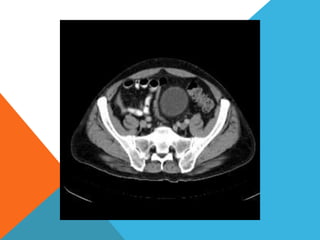

El paciente presentó síntomas de sangrado digestivo y pérdida de peso. Exámenes revelaron gastritis crónica asociada a H. pylori. Un tumor fue descubierto en una colonoscopia normal. La cirugía removió un tumor fibroide solitario, una rara neoplasia mesenquimal que usualmente crece lento y tiene bajo potencial de malignidad. El pronóstico después de la remoción quirúrgica es generalmente bueno.